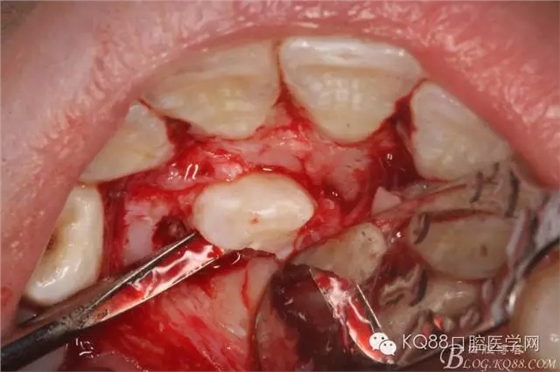

圖6.翻瓣:看到腭側(cè)骨面隆起

圖7.在隆起骨面的最高點(diǎn)為去骨點(diǎn)去骨、逐漸暴露13牙冠

圖8.暴露出來的13牙冠的舌面